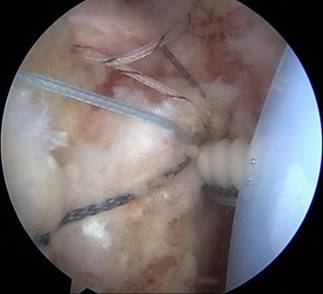

另外,微创成为我院关节科的一大亮点,膝关节周围截骨术,单髁置换术都是微创手术,患者创伤小,恢复快。我院关节科采用直接前路微创髋关节置换术,切口小,只有8-10cm,顺肌间隙进入,不切断任何肌肉,出血少,无痛,关节脱位率低,术后康复快。关节镜下微创肩袖撕裂修补,冻结肩松解,肩关节撞击症肩峰下减压术,膝关节交叉韧带损伤修补等手术,避免大切口、大创伤、恢复快。

关节镜下肩袖损伤修复术治疗肩袖损伤

优点:损伤小、恢复快。